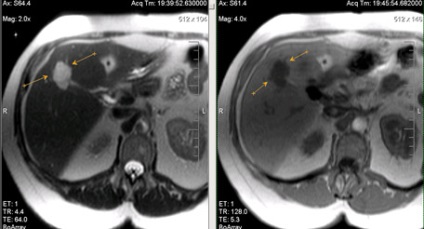

Hepatocelluláris rák (az US - hemangioma).

Hepatocelluláris rák (infiltratív formájában), a másodlagos lymphadenopathia.

Egyedi kis májáttétek; hasonlóság a natív vizsgálat hemangiomas.

Ugyanez a beteg. Postkontrastnye tomográfia. Egyedi kis májmetasztázisok ellentétben hemangiomas tomogramjait a korai és a késői fázisban válik parenchymás hypointense a natív vizsgálat (gyors enyhülést kontraszt kritérium 1 perc).